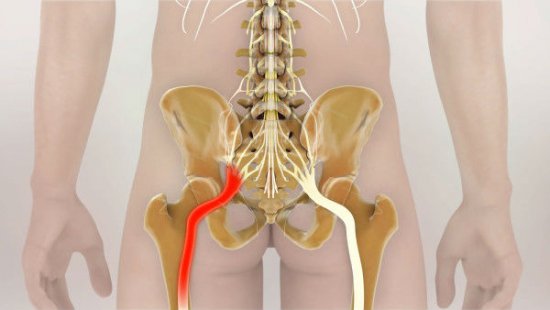

Защемление седалищного нерва

Чаще всего боли в спине появляются при проблемах с позвоночником

Таким образом, причина болезненности не всегда кроется в поражениях опорно-двигательного аппарата. Если боль вызвана нарушением функции внутренних органов, то она имеет иррадиирущий характер. Кроме того, у мужчин болит спина внизу позвоночника при хроническом простатите, раке предстательной железы, хотя этот симптом не всегда обязателен.

Люмбоишиалгия — проявляется резкими, пронизывающими болями, которые отдают в нижние конечности. Может быть симптомом межпозвоночной грыжи. При появлении люмбоишиалгии не следует откладывать визит к врачу. Своевременное лечение поможет избежать серьезных осложнений.

Признаком неблагоприятного исхода является люмбалгия, которая проявляется спектром разнообразных симптомов. Боли по ходу нервного корешка могут отдавать в ягодицы и ступни. Дискомфорт появляется при наклонах (даже при наклоне головы вниз), смехе, кашле и т. д. Болевой синдром усиливается при поднятии лежа на спине прямой ноги.

Как проявляются боли в пояснице

Симптоматика болей в спине носит разносторонний характер и зависит от имеющейся патологии. При растяжении боль проявляется в виде спазмов, движения при этом ограничены. Болевой синдром иррадиирует в ягодицы, заднюю часть бедер. Пациенту трудно наклоняться, совершать повороты корпуса. При повреждении корешков боли отдают в нижнюю часть тела, может быть нарушение чувствительности, онемение.